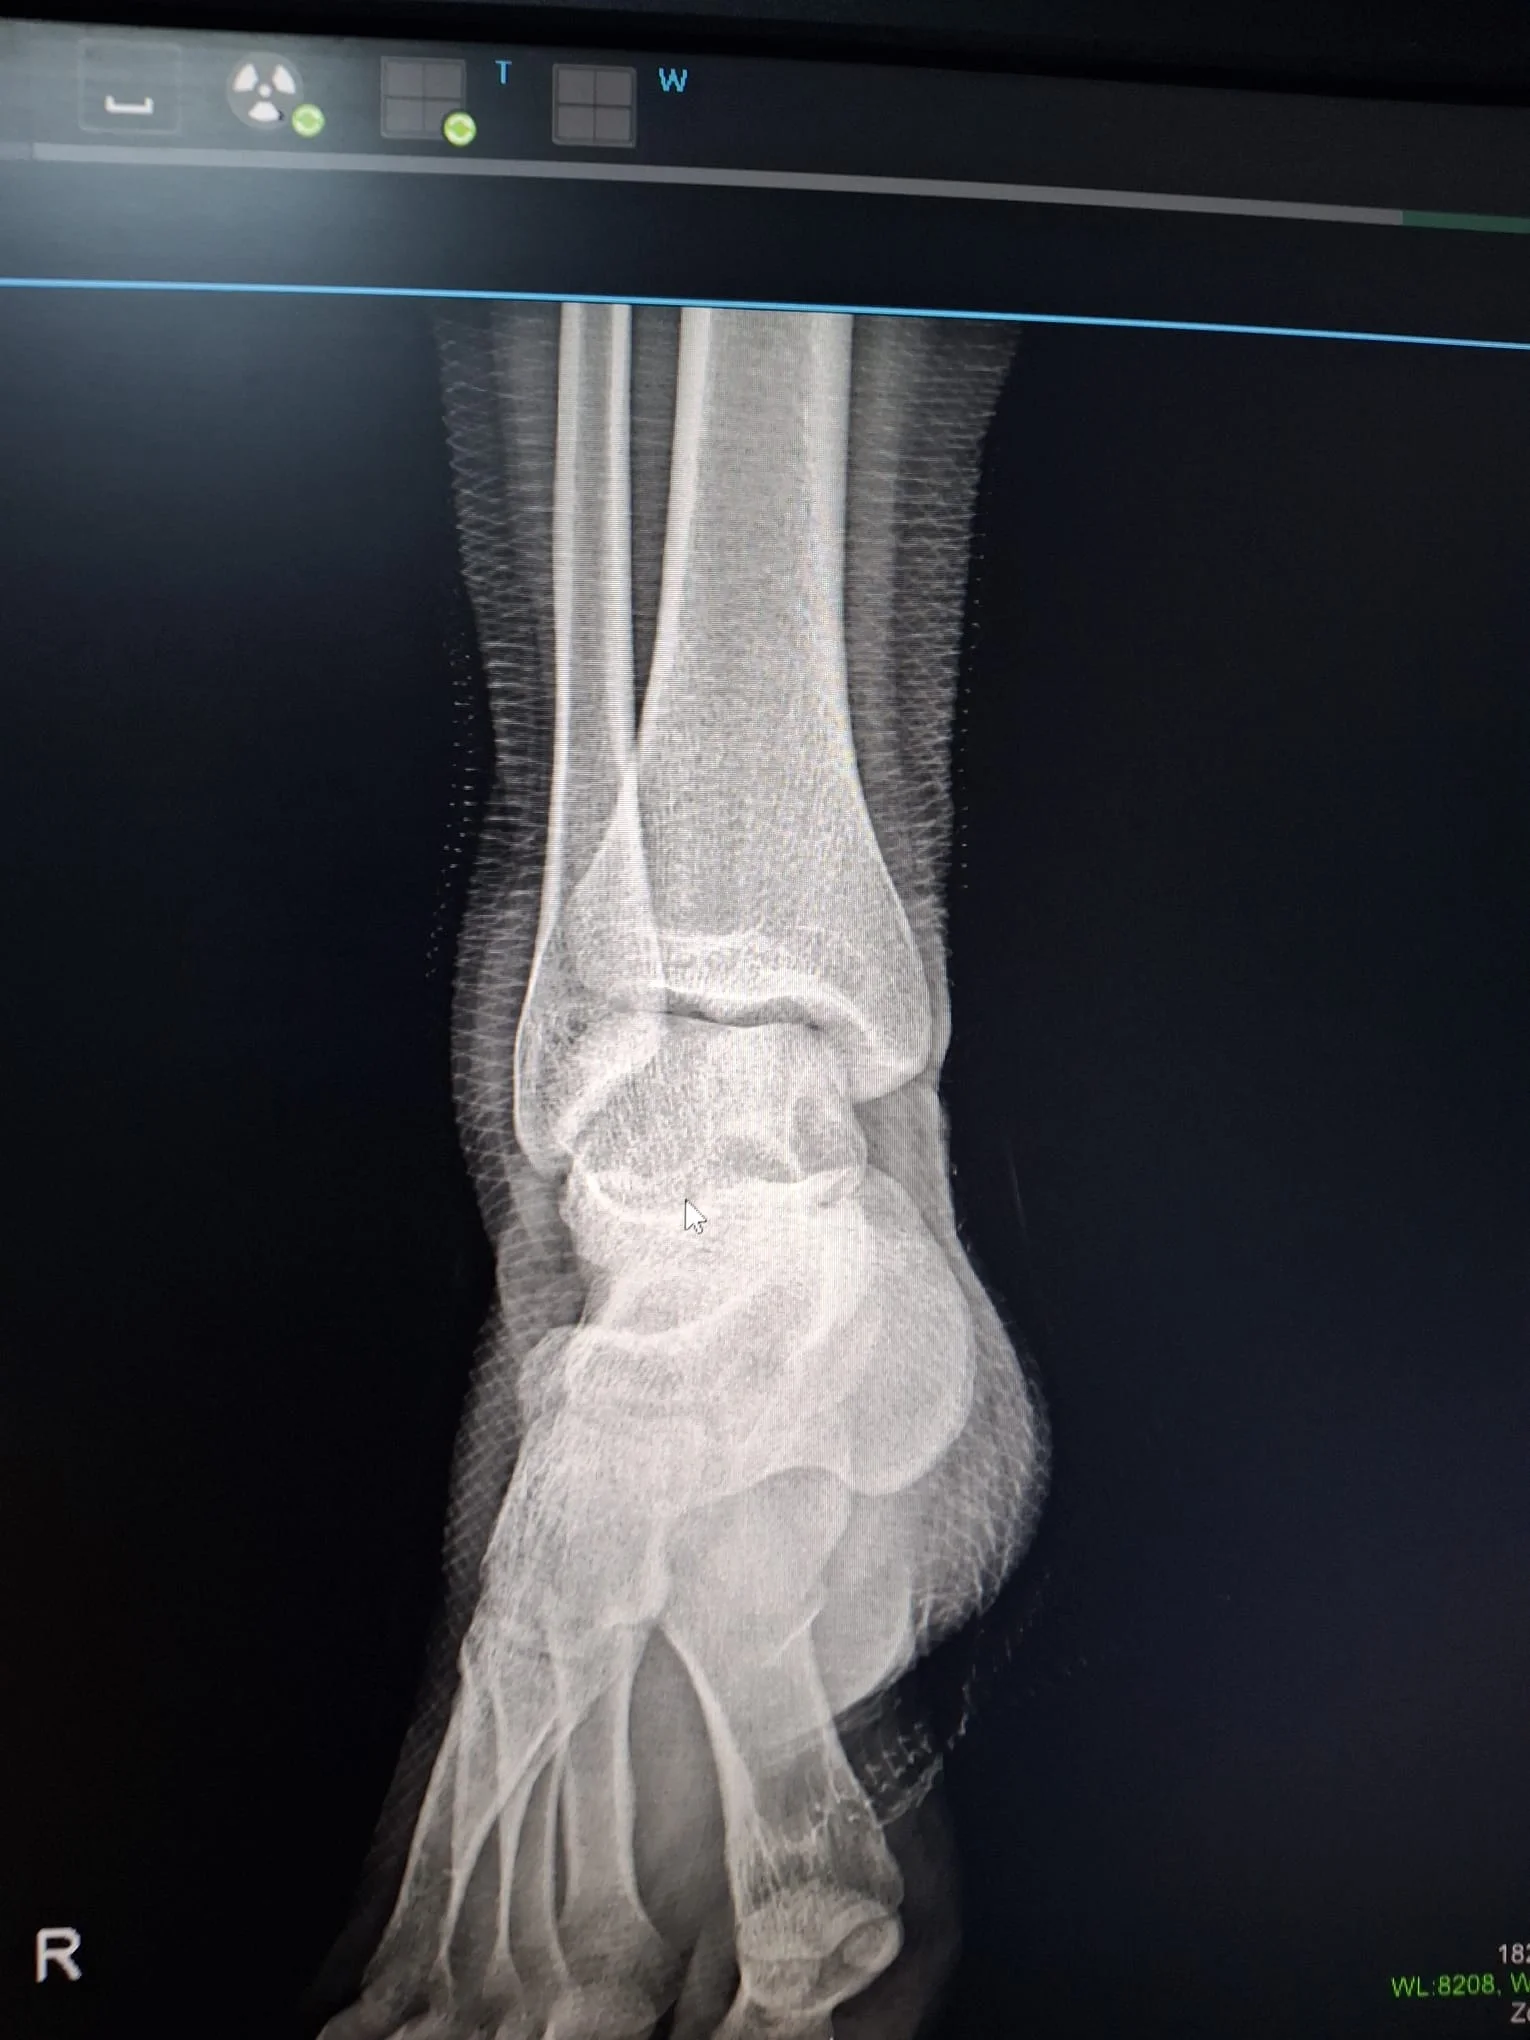

merdivenden düştüm ve bileğimi burktum ortopedi okuyan veya tıp okuyan arkadaşlar röntgeni yorumlayabilir mi kırık çıkık var mı

kırık yada çıkık yok eğer ağrı sızı varsa büyük ihtimalle doku zedelenmesi vardır